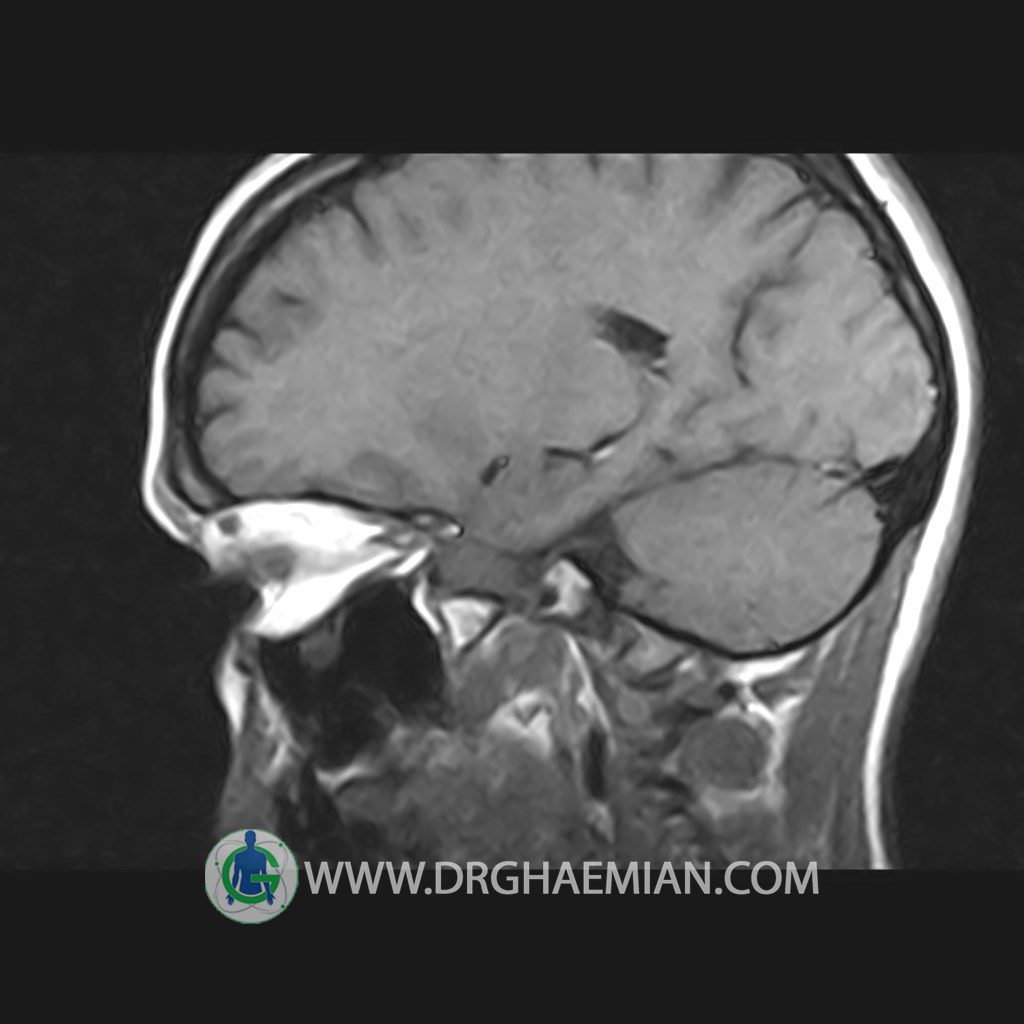

پزشکان اغلب از تصویربرداری ام آر آی برای تشخیص و درمان عارضه های پزشکی که فقط با استفاده از اشعه ایکس یا میدان مغناطیسی و امواج رادیویی قابل مشاهده است، استفاده می کنند. دستگاه ام آر آی تصاویر دقیق از ساختار های داخلی بدن ایجاد می کند. در این کیس هیپرپلازی هیپوفیز و آدنوم مشاهده می شود.

HYPOPHYSIS MRI

(with and without contrast)

Technique: Axial , coronal T1 , Axial , coronal , sagittal T2 , Axial, coronal T1 post Gd & 64 dynamic thin coronal slices.

The sella shows normal size , position and configuration .

The borders of its floor and walls are smooth and sharply defined .

The infundibulum is centered and of normal size .

The optic chiasm and suprasellar spaces appear normal .

The cavernous sinus and imaged portions of the internal carotid artery and carotid siphon are unremarkable .

Evaluable portions of the neurocranium show no abnormalities .

The sphenoid sinus is clear and pneumatized .

– Mild convexity at superior border of pituitary gland with post contrast homogeneous enhancement suggestive for pituitary hyperplasia & iso signal adenoma

is seen